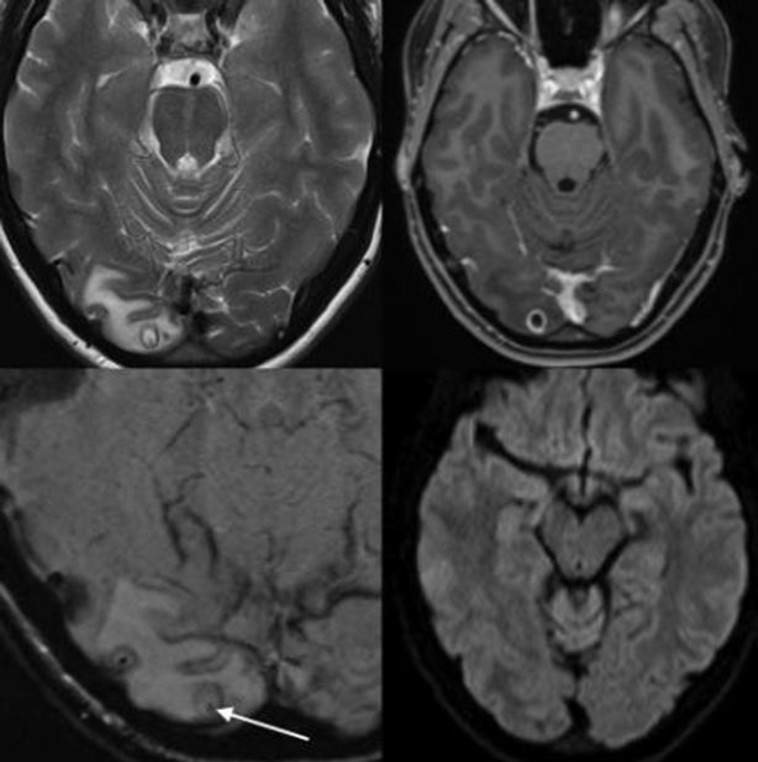

מתוך צילום ה-MRI של האוסטרלית

מתוך צילום ה-MRI של האוסטרלית | צילום: The American Journal of Tropical Medicine and Hygiene

מצבה של האישה מכונה "Neurocysticercosis" והוא יכול לגרום לתסמינים נוירולוגים כאשר שהזחלים מתפתחות בתוך מוח האדם. בדרך כלל, הסיכון הממשי הוא לא גבוה אך הכאבים שיכולים להיגרם מכך עלולים להיות חמורים. לאחר הניתוח שעברה הצעירה, היא החלימה מהר ללא צורך בתרופות.